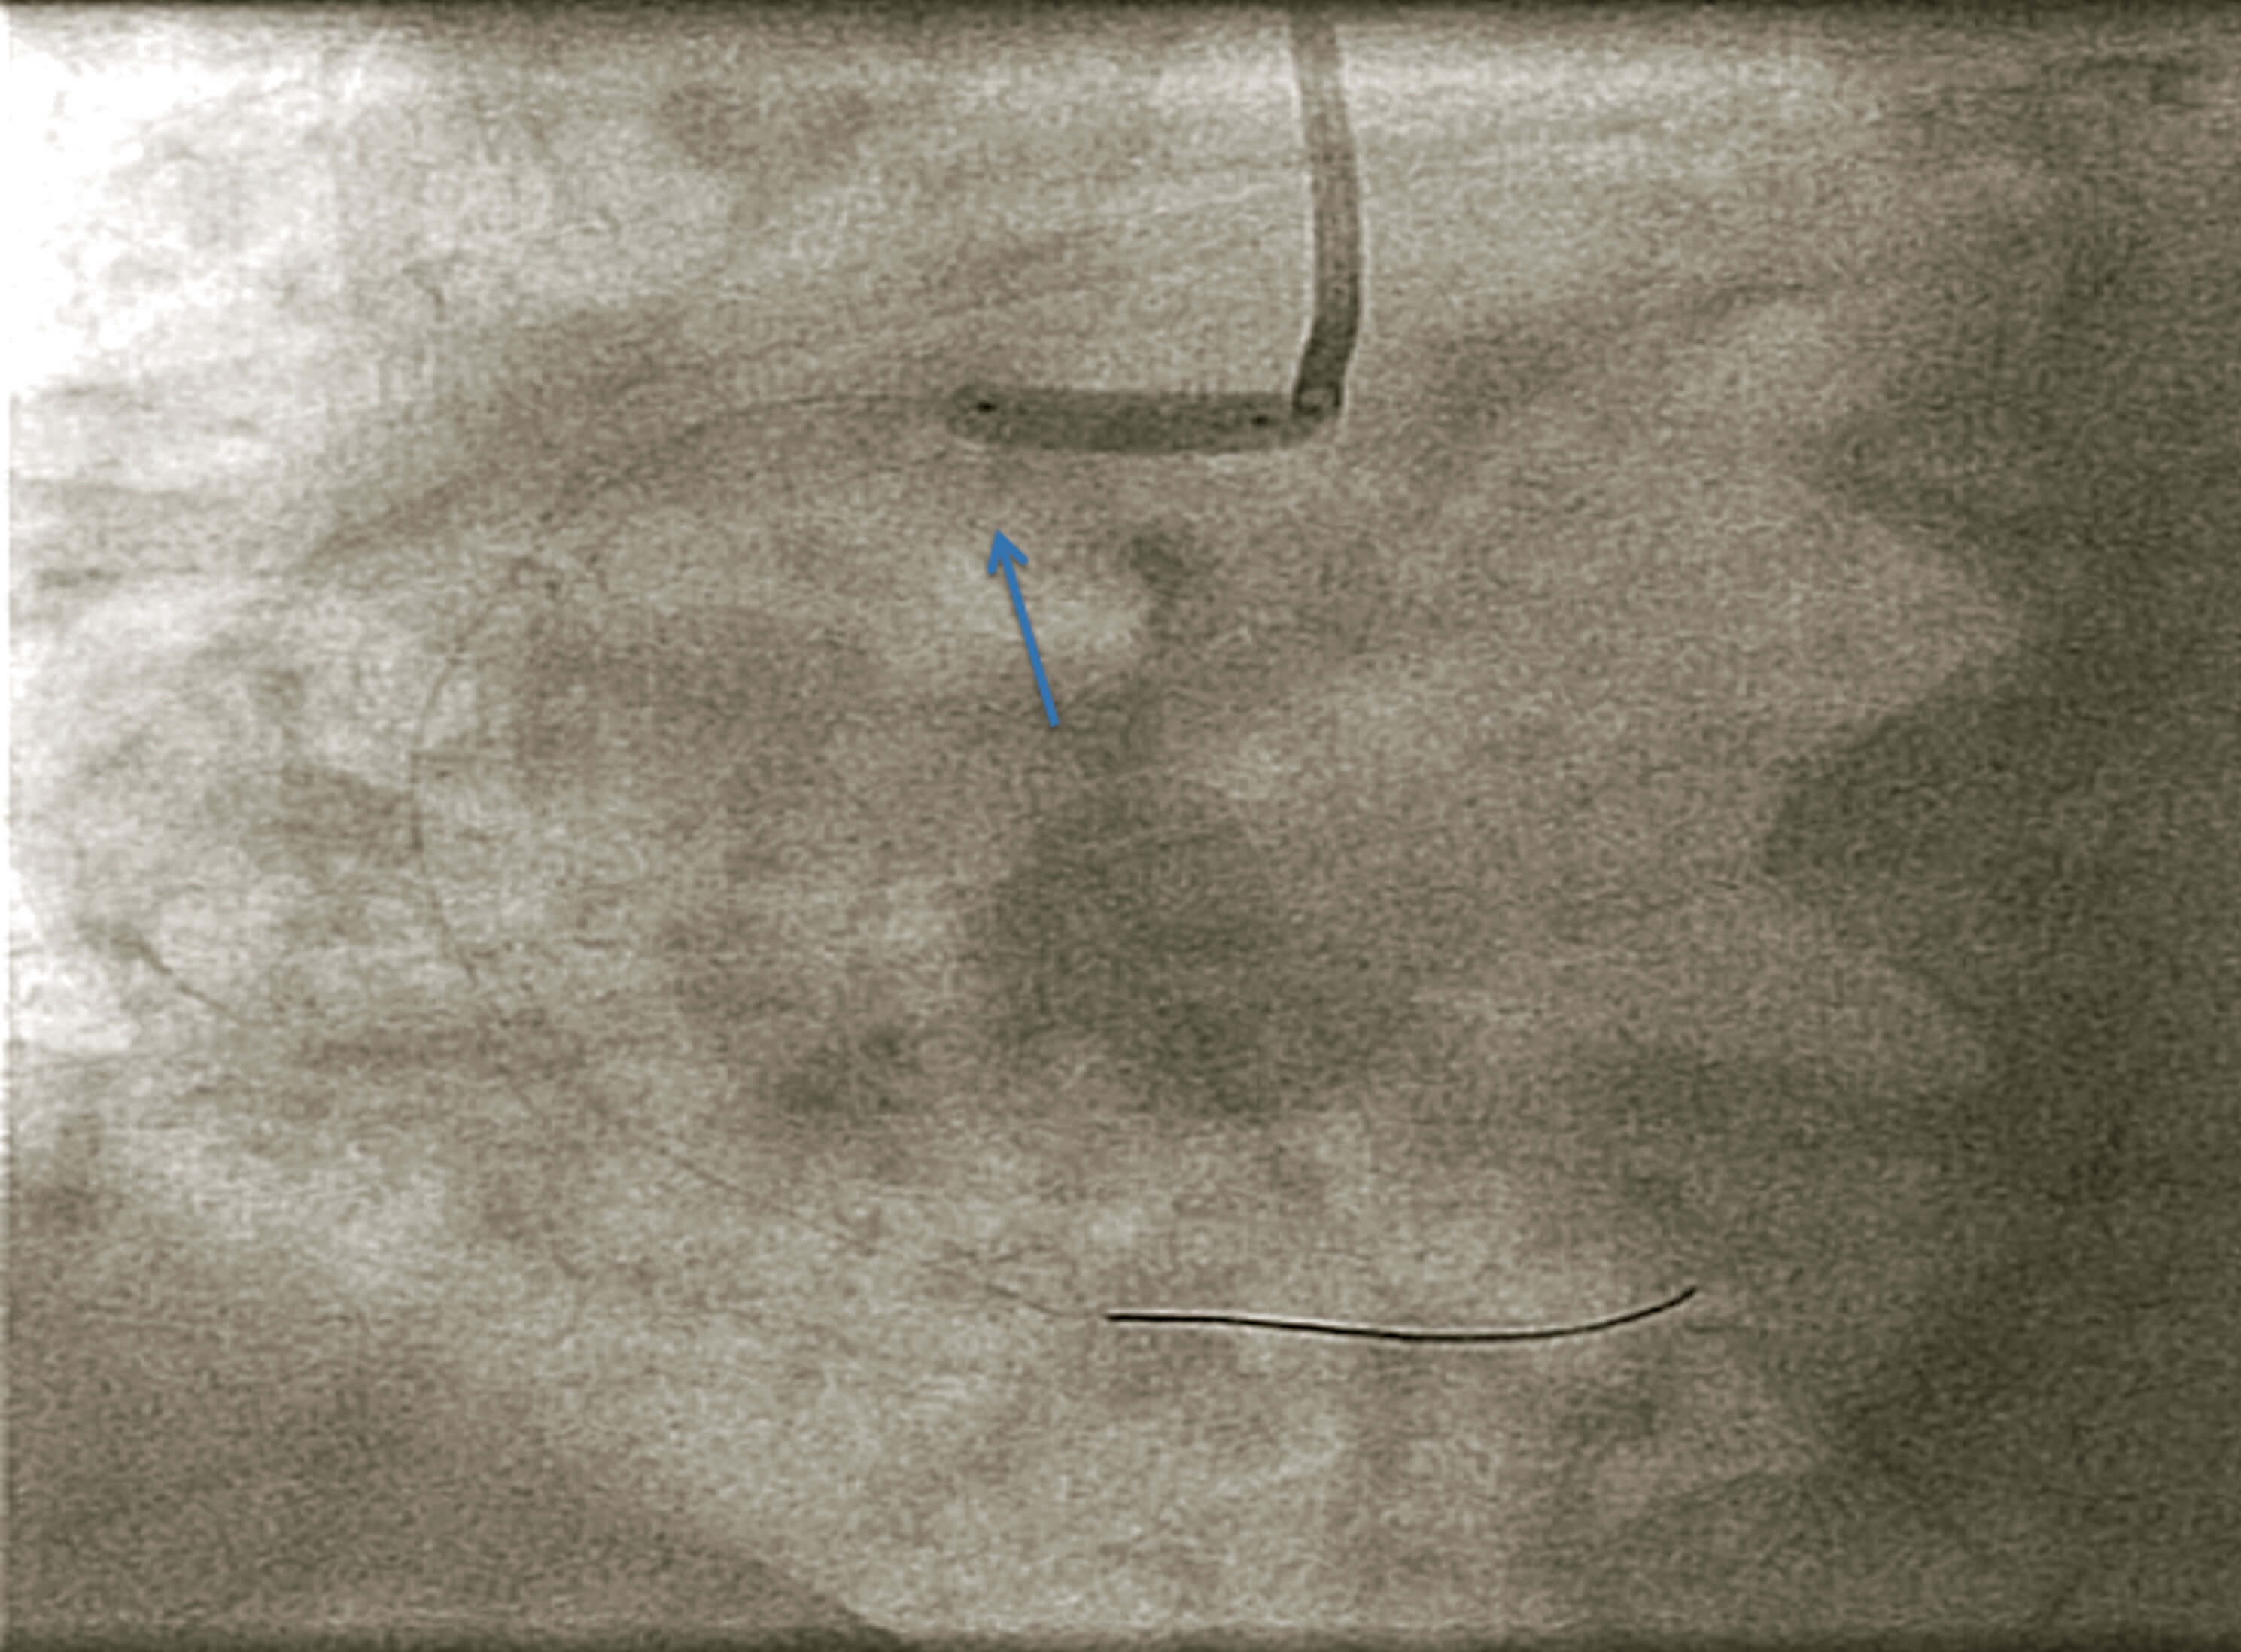

En el momento del implante, y estando el stent inflado a 6 atm, el paciente (dentro del cuadro de agitación que presentaba dada su situación hemodinámica) realizó una inspiración profunda y se produjo un desplazamiento del stent hacia la aorta (figura 4), que pareció haberse implantado totalmente fuera del ostium de la arteria coronaria derecha.

Figura 4. Se observa el stent desplazado hacia la aorta. La flecha señala la marca del calcio en el seno de Valsalva.

Por tanto, nos encontrábamos ante un stent infraexpandido, desplazado o suelto en la aorta, que nos dificultaba la navegabilidad, con un trombo sin cubrir en una lesión compleja ostial, en un contexto clínico de síndrome coronario agudo.